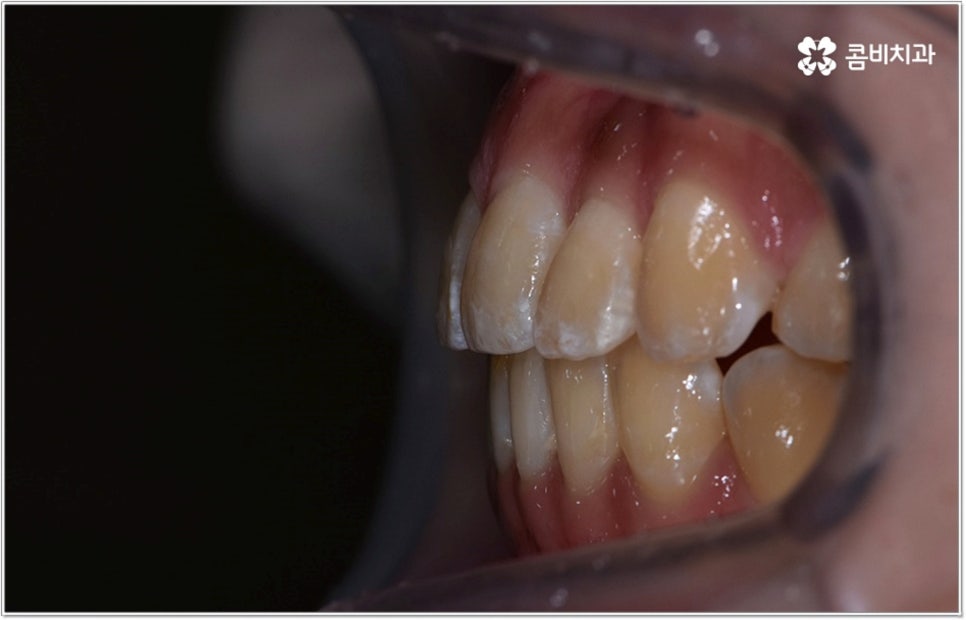

특히 위아래 치아가 제대로 맞물리지 않는 분들 중 시간이 지날수록 치열이 비정상적인 저작 과정에 적응하는 쪽으로 영향을 받아 부정교합의 정도가 심해지고 턱관절 건강까지 악화되는 일이 발생할 수도 있기 때문에 주의하실 필요가 있는데요. 미리 크게 걱정을 하거나 지레 짐작으로 막연하게 두려움을 가지고 내원 자체를 미루시기 보다는 현재 자신의 상황이 어떤지부터 먼저 상세하게 체크해보고 그에 따라 필요한 치료 과정이 무엇인지도 한 번 알아두면 좋겠다는 마음으로 치과에 방문하셔서 부정교합의 종류 (주걱턱, 돌출입, 덧니, 개방교합 등) 와 정도를 꼼꼼하게 검사한 후 숙련된 의료진과 차근차근 상담을 해보시면 부정교합으로 인한 불편함을 줄이는데 도움이 되실 거예요.

잘 아시다시피 교정이란 치아에 교정 장치 (브라켓) 를 부착하고 와이어에 교정력을 걸어 필요한 방향으로 치아를 이동시킴으로써 고른 치열과 올바른 교합을 가진 정상적인 구강 구조를 회복하는 치과 진료를 의미하는데요, 말씀드린 것처럼 부정교합에는 다양한 형태가 있고 또한 환자분들마다 심각한 정도가 모두 다르기 때문에 현 상태를 면밀하게 체크하고 맞춤 교정 치료 계획을 세우는 것이 무엇보다 중요하다고 할 수 있습니다. 즉 3D CT 와 같은 정밀 진단 장비를 갖추고 있는 치과에서 교정 관련 임상 경험이 풍부한 숙련된 의료진과 함께 치료를 진행하는 것이 필수적이라고 할 수 있어요. 전체 방향 및 세부 플랜을 세울 때 각 환자에 맞게 치아의 이동 속도에 무리가 가지 않도록 하기 위해서 연령이나 발달 상황, 진행 상황을 면밀하게 살펴보는 것이 필요하며 또한 구강 내 공간 유무 및 부정교합 정도에 따라 발치 또는 비발치치아교정 여부를 결정하게 될 거예요.

만약 치아가 이동할 범위를 계산해 봤을 때 공간이 충분하다면 굳이 치아를 뽑지 않고 비발치치아교정 과정으로 치료할 수 있어요. 제일 뒤에 있는 어금니를 더 후방으로 이동시키거나 치간 삭제, 악궁확장장치 등으로 치아 사이를 벌려서 이동 공간을 확보할 수 있으면 비발치치아교정 이 가능한 거예요. 이 때 부정교합이 심각하거나 악골이 치아에 비해 많이 작은 경우, 구조적인 원인을 개선할 필요성이 있는 경우 등 발치 교정을 하는 것이 꼭 필요한 케이스라면 치아를 뽑아주어야 하며, 환자분들의 상황에 따라 다르지만 보통은 소구치를 발치하는 경우가 많이 있습니다.